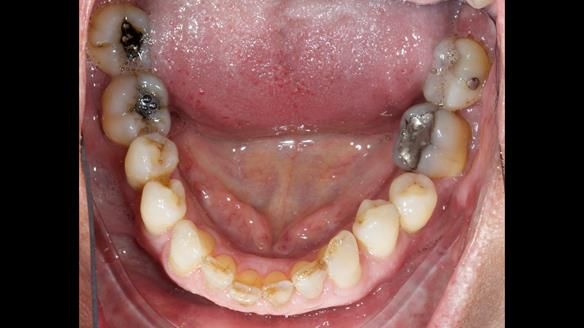

Welcome to Newsletter 64. I'll walk you through the process of providing a Mk 2 metal-based partial denture (RPD), for Ian a retired Veterinary Surgeon aged 78. The RPD was made at an increased vertical dimension and acted as an occlusal stabilisation splint - reducing the wear and bite force on the remaining natural teeth.

Ian was referred to me by his general dentist.